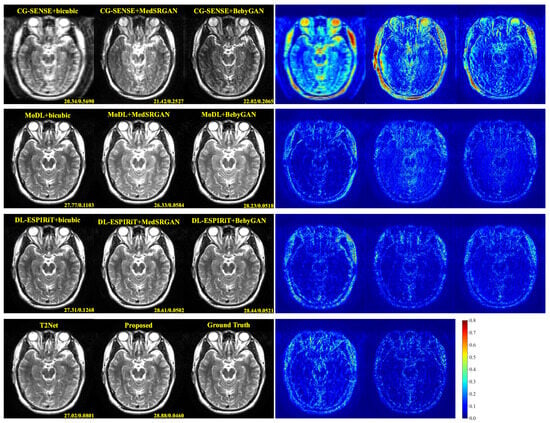

For a more intuitive comparison, we provide visual comparisons for each method. In Figure 5 and Figure 6, we illustrate the axial and sagittal views of the 2D brain dataset, respectively. In Figure 7 and Figure 8, we display the brain image and neck image of the 3D VWI dataset. For each method, we show the restorations along with the corresponding error maps. The images are placed on the left, the error maps on the right, and the PSNR and LPIPS metrics of each image are shown at the bottom right corner. From the error maps, it is evident that our proposed method consistently produces high-quality results with improved visual fidelity and better retention of structural information compared to the other methods.

Figure 8. Visual comparison of each method for a neck image in the VWI dataset.